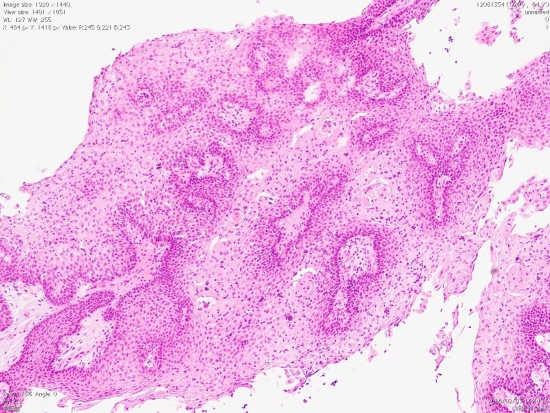

乳頭状頭蓋咽頭腫 papillary craniopharyngioma

- 成人のみに発生する良性の頭蓋咽頭腫です

- adamantinomatous typeとは異なった腫瘍ではないかと思えるくらい違います

- 平均年齢は40-55歳くらいで中年以降です

- 第3脳室内部に発生します

- ですからトルコ鞍内腫瘍でも鞍上部腫瘍でもありません

- 画像診断では,第3脳室内に,境界明瞭な,ガドリニウムで全体が増強される,石灰化ものう胞も無い腫瘍として診断されます

- 石灰化がありません

- 固形腫瘍であり,のう胞形成はとてもまれです

- ですからコレステロールを含む機械油のような内容液がありません

- adamantinomatous typeと比較して脳組織浸潤が少ないです

- 病理は,fibrovascular coreを中心として,ケラチンを含まない分化度の高い”非角化型”扁平上皮の単純な増殖です

成人の第3脳室内部に局在する頭蓋咽頭腫です。経脳梁法で両側のモンロー孔から全摘出しました。下垂体組織は残っています。これは乳頭状頭蓋咽頭腫と呼ばれるもので,成人にしか発生しません,のう胞がなく石灰化もないのが大きな特徴です。境界が明瞭で柔らかく摘出が簡単なタイプとして知られています。この患者さんも術後に下垂体機能不全も視床下部障害も生じませんでした。

Monomorphous mass of well-differenciated squamous epithelium lacking surface maturation and wet keratin.

摘出した骨化片の病理像です。成熟した骨組織 mature boneです。

adamantinomatous typeです。mature boneの端には破骨巨細胞が多数見られます。

鞍内にあった部分の病理所見です。adamantinoomatous typeで,破骨細胞を伴う強い骨化がみられます。